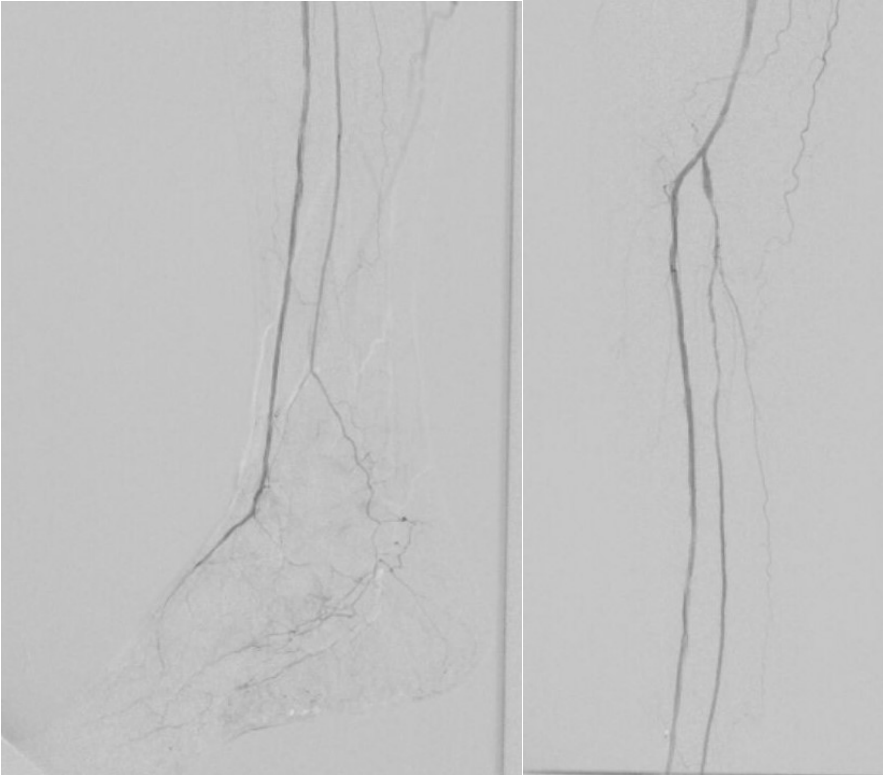

7. 术后造影血流恢复

本例患者股浅动脉重度闭塞,股浅远端重度钙化病变近收肌管,利用Shockwave冲击波球囊获得满意的管腔准备后联合使用DES,为保障远期通畅植入支架,支架膨胀形态理想。